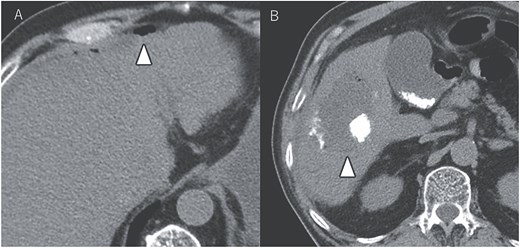

A 72-year-old man presented with abdominal pain. Computed tomography (CT) revealed a liver tumor in segment six/five, abutting the transverse colon without invading. Enlarged lymph nodes in regions 12b and 16b1 were noted, but there were no lung metastases or ascites. Magnetic resonance imaging revealed multiple nodular lesions in liver S6/5 with low signal intensity on T1-weighted images, and mosaic-like high signal intensity on T2-weighted images (Fig. 1). Based on these findings, the diagnosis of HCC was made, staged as cT2N1M1 Stage IVB. The patient underwent transarterial chemoembolization (TACE) followed by ATZ + BV therapy, resulting in tumor and lymph nodes reduction (Fig. 2).

Magnetic resonance imaging showing multiple nodular lesions in liver S6/5 with low signal intensity on T1-weighted images (A), and mosaic-like high signal intensity on T2-weighted images (B).